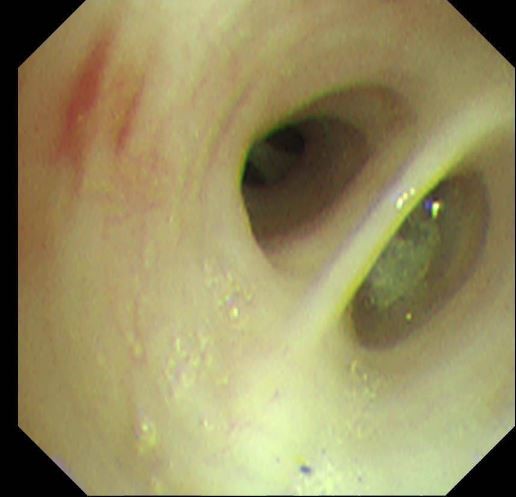

两天后复查支气管镜,发现患者左下叶背段远端细支气管仍有残留泥沙样异物。团队采用超细支气管镜联合冷冻技术,通过冷冻探头将异物凝固,再用超细活检钳逐支清理,实现对远端气道的彻底清理,实现气道“零死角”。

(超细支气管镜见左下叶背段远端支气管泥沙样物质)